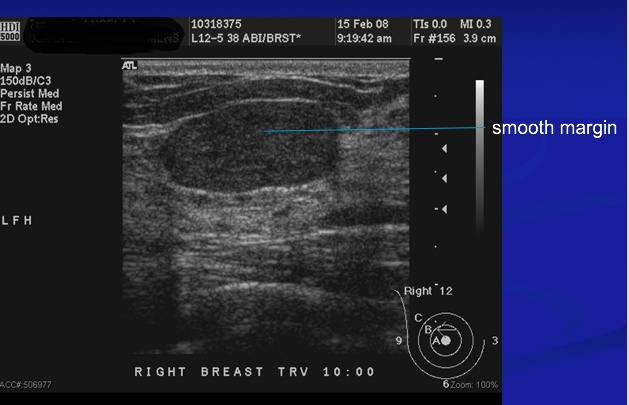

Fibroadenoma

_is a benign tumor of fibrous tissue and glands that is the most common benign neoplasm of the breast. It most commonly occurs in women in their 20s and 30s.,

_The clinical presentation includes:

Painless (less commonly painful) and well circumscribed: distinct from rest of breast

Mobile marble-like mass, smooth, firm

Estrogen-sensitive (grows during pregnancy, and may be painful during the menstrual cycle, shrink during menopause)

May involute or calcify after menopause.,

Fibroadenoma: noncalcified rounded mass in UOQ left breast

Wider than tall

breast cancer grow vertical